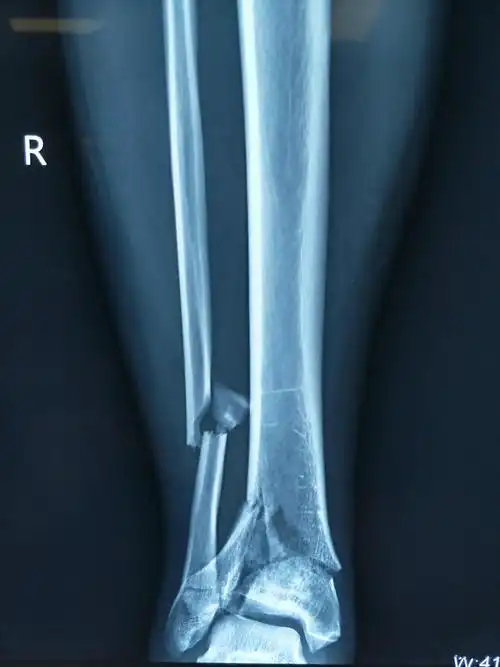

胫骨粉碎性骨折有可能完全恢复正常吗